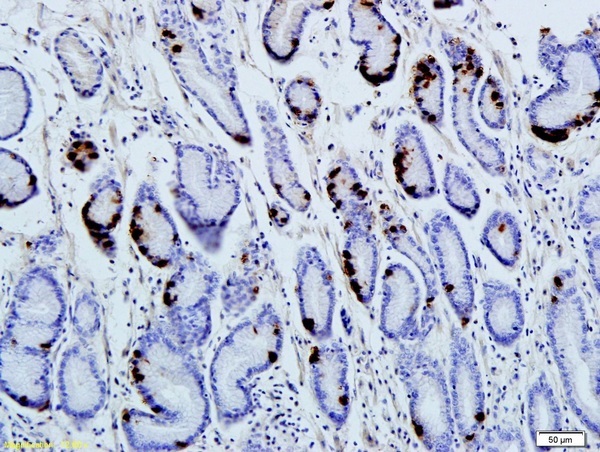

- Main image

- Experimental details

- Formalin-fixed and paraffin embedded human gastric parietal cells labeled with Anti-Gastrin Polyclonal Antibody, Unconjugated (bs-1189R) followed by conjugation to the secondary antibody and DAB staining

- Sample type

- Other comments

- Stomach